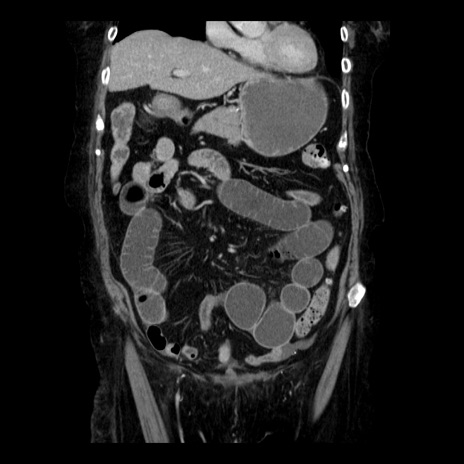

症例14(冠状断像)

【症例】 90歳代女性

【主訴】 腹痛・嘔吐

【現病歴】今朝から左側腹部痛を認めた。 経過観察していたが、嘔吐を認めたため来院。

【既往歴】 子宮癌術後

【身体所見】 意識清明、BP 127/54mmHg、P 98bpm Sp02 95%(RA)、BT 35.8°C、腹部平坦・軟腸ぜん動音聴取良好、右下腹部圧痛(+) 反跳痛なし

【データ】WBC 9800、CRP 0.46